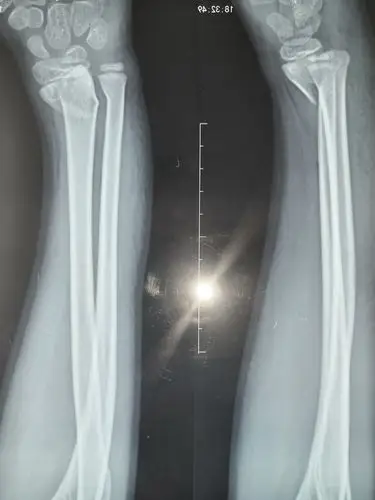

你好,三周前,我从高处跳下,伤到了脚踝,请您帮我看看x光片,看是哪里

摄片显示骨折,移位明显